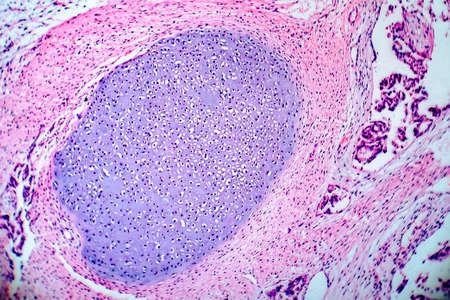

Low magnification of a human prostate gland in a 70-year-old man. The prostate gland appears with dilated alveoli, which contains many corpora amylacea (prostatic concretions) in their lumen. Light microscope micrograph. Hematoxylin & eosin stain.